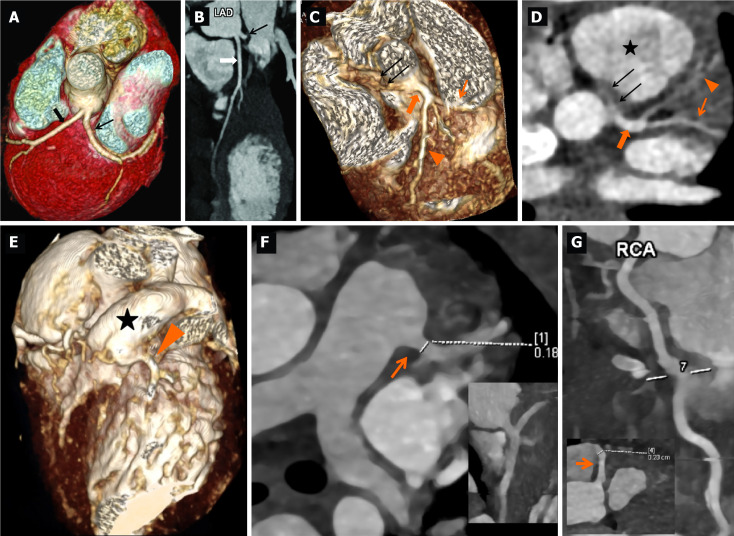

Results: Of the 241 patients with KD who underwent CTCA, 3 (1.24%) had congenital coronary artery anomalies on CTCA detected incidentally. In all 3 patients, baseline 2DE had identified CAAs. CTCA was then performed for detailed evaluation as per our unit protocol. One (11-year-boy) amongst the 3 patients had complete KD, while the other two (3.3-year-boy; 4-month-girl) had incomplete KD. CTCA revealed separate origins of left anterior descending artery and left circumflex from left sinus [misinterpreted as dilated left main coronary artery (LCA) on 2DE], single coronary artery (interpreted as dilated LCA on 2DE) and dilated right coronary artery on 2DE in case of anomalous origin of LCA from the main pulmonary artery. The latter one was subsequently operated upon.